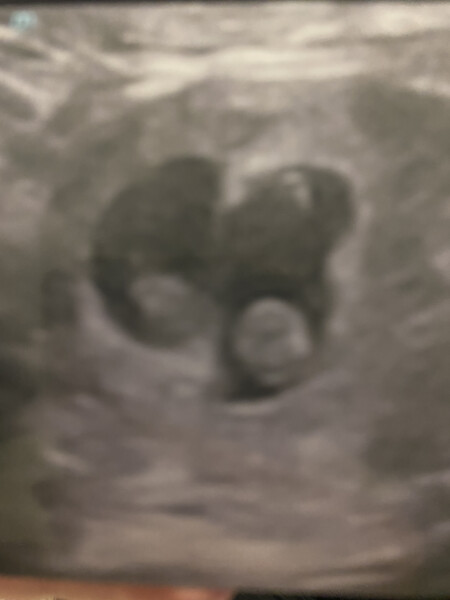

Went for our early reassurance scan today.

Thankfully all is well with BOTH babies. We found out today we're having non identical twins 😁♥️.

I'm 8+7 today. Both measuring on track, touch wood x